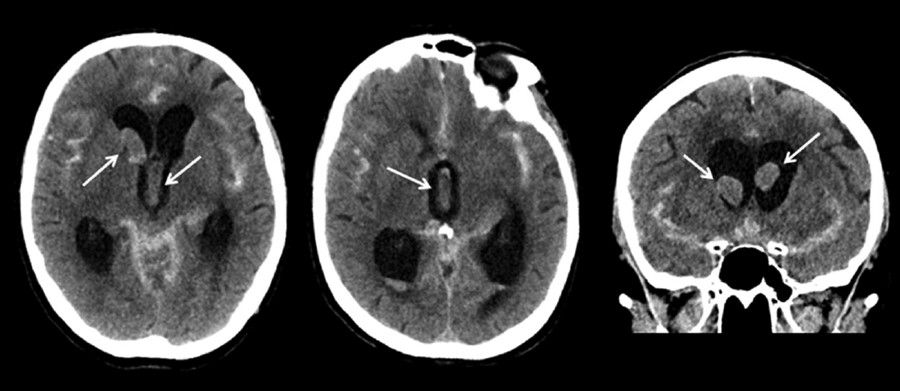

头颅CT检查报告:颅骨完整;脑实质内无明显密度及形态异常改变区;脑室、脑池、脑沟无明显异常;中线结构居中。提示:颅脑CT平扫未见明显异常,请结合临床,短期随访!处理:入抢救室,心电监护,给予合贝爽等治疗。9月13日,宣布临床死亡。

患者死亡后,家属携9月6日CT片前往他院请专家读片,诊断为蛛网膜下腔出血。患方认为医师缺乏临床经验和工作责任心,对常见病不能采取正确治疗措施,存在明显失误。